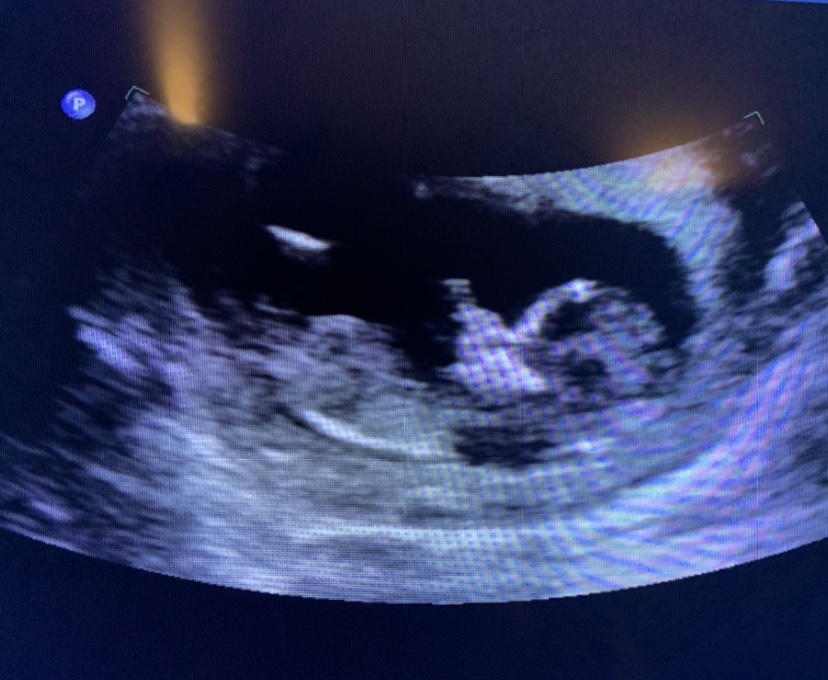

Boy nub, right? 12+2

Had my first trimester scan today. Have to go back as the baby never stretched out to get the proper measurements. The tech gave us this one photo. I’m pretty sure I can see an obvious boy nub (I was really hoping to not see any nub but oh well), but figured I’d put it up for confirmation. I’m feeling a bit upset as this is our third and last baby and we already have two boys...so I was really hoping for a girl. But I know I’ll get over it and love our third son.

Baby is 12w2d today (not sure what it was measuring today due to its position though.)

Hi again. I added an arrow to the spot where I assumed the nub is. Is it not actually a nub after all?

I think that might be too high up to be the nub but not sure as the image isn’t very clear. Not sure I can see a nub here. Fingers crossed for a clearer picture at your next scan